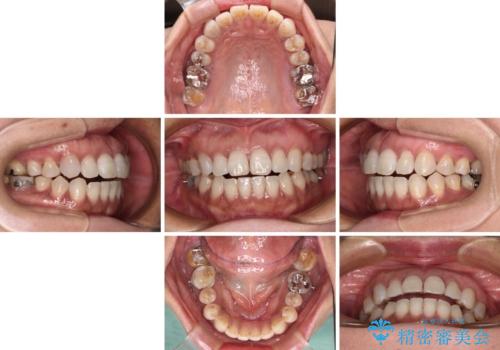

極端な上下前歯の開咬を改善 オープンバイトのインビザライン矯正

- 上下前歯の隙間を気にして来院された患者様です。

開咬の治療は、前歯を閉じるように動かすとともに、上下臼歯を圧下(骨内にめり込ませる)させることで進めて行きます。

インビザラインは臼歯の圧下を効果的に行えるため、インビザラインを用いて矯正治療を行うこととしました。

治療前に、いくらインビザライン矯正がオープンバイトを得意としているとは言え、さすがに限界があるだろうと思っておりましたが、前歯でレタスが噛めるまで改善することができました。

顔の印象も大きく変わり、患者様には大変満足していただきました。